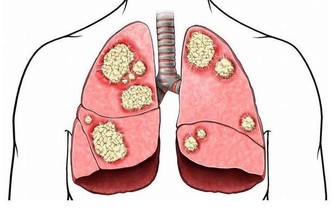

舌癌是第一大口腔癌,也被視為「全球第六高發癌症」,

多好發於抽菸者、牙齒不好者、飲食過辣過燙者。